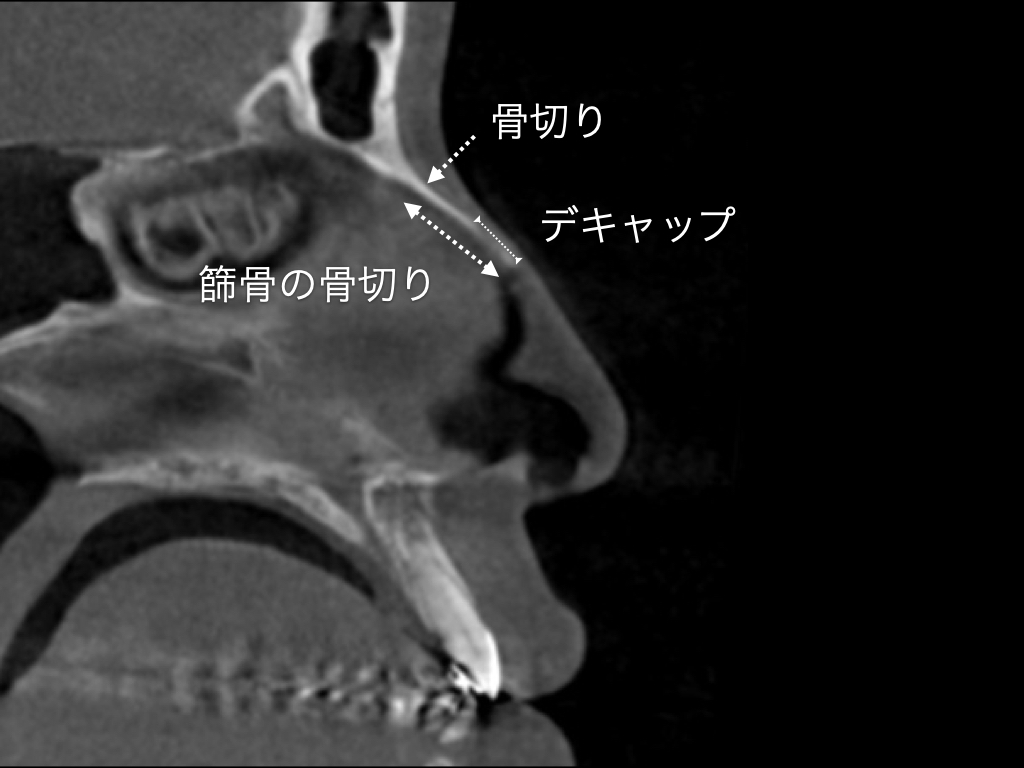

今回,プッシュダウンタイプの骨切りにより鼻背を真っ直ぐにします.肋軟骨による鼻中隔延長を行い 約6mm前方に移動します.そのままですと大きなサイズ感の鼻になりますので,鼻翼基部ならびに鼻柱基部に肋軟骨を挿入して,全体を前方に移動させる予定としました.